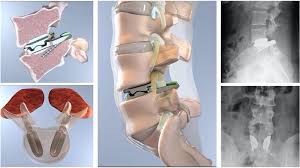

Spine surgery can fail if there is recurrence of slip disc even after disc removal surgery. This can occur either at the same level or some other level. Sometimes, spine surgery can fail due to failure to use spinal implants at the time of first surgery. Rarely, spine surgery can fail if the attempted union between the bones at the time of first surgery fails to materialize resulting in nonunion or implant failure. Another reason for failure of spine surgery can be progression of the degeneration in the spine to levels above and below the previously operated level.

Very commonly, we get patients with a failed previous spine surgery performed in their home country. We routinely perform revision surgery on such cases and ensure that their spine problem is solved and their problems are taken care of. To ensure maximum success in such complex cases we use new technology namely Carm, Pedicle screw instrumentation, High Speed Burr, Microscope, Navigation and Neuromonitoring to make even revision spine surgery highly successful. We have a lot of experience in dealing with such revision spine surgery cases and we can ensure successful outcomes even in these complex cases.